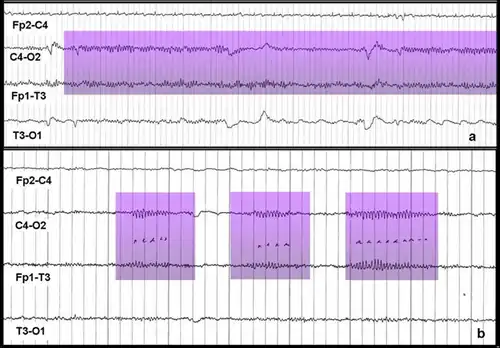

Мю-ритм (μ-ритм, роландический ритм, сенсомоторный ритм, аркоидный (arceau) ритм, аркообразный (wicket) ритм, гребенчатый ритм, дугообразный ритм) — ритм головного мозга — периодические колебания биопотенциалов в сенсомоторной области коры головного мозга на частоте 8 — 13 Гц (чаще всего 9 — 11 Гц). Эти колебания могут быть зарегистрированы методами электроэнцефалографии (ЭЭГ), магнитоэнцефалографии (МЭГ), или электрокортикографии (ЭКОГ). Наиболее выражен в состоянии физического покоя. В отличие от альфа-ритма, который возникает на аналогичной частоте в задней части головы над зрительной корой также в состоянии покоя, мю-ритм локализован над моторной корой. У человека подавление мю-ритма происходит, когда он или она выполняет какое-либо движение или, после определённой тренировки, когда он или она визуализирует (представляет) выполнение движений. Это подавление называется десинхронизация (уменьшение амплитуды сигнала), потому что причиной появления ритмических паттернов на ЭЭГ является синхронная активность большого числа нейронов. Кроме того, мю-ритм подавляется когда человек наблюдает за выполнением движений другого человека. Рамачандран и его коллеги предположили, что это является признаком того, что зеркальная нейронная система участвует в подавлении мю-ритма[1][2], однако, есть и противники этой теории[3]. Мю-ритм представляет интерес для множества учёных. Например, при изучении развития нервной системы, интерес представляют подробности формирования мю-ритма в младенчестве и детстве и его роль в процессах обучения[4]. Поскольку некоторые исследователи считают, что расстройства аутистического спектра (РАС) во многом связаны с изменениями в системе зеркальных нейронов[1][5][6], и что подавление мю-ритма отражает активность зеркальных нейронов[2], многие из этих учёных заинтересованы в изучении мю-ритма у людей с расстройствами аутистического спектра. Мю-ритм широко используется при построении мозг-компьютерных интерфейсов (МКИ). С развитием МКИ систем, врачи надеются дать людям с тяжёлыми инвалидностями новые способы коммуникации, средства для манипулирования и перемещения в пространстве[7].

Интерфейсы мозг-компьютер (ИМК) — активно развивающаяся технология, которая, как полагают, однажды сможет дать бо́льшую независимость людям с инвалидностями. Предполагается, что эти технологии смогут помогать людям почти полностью или даже полностью парализованным, например с такими заболеваниями как тетраплегия (квадриплегия) или боковым амиотрофическим склерозом. ИМК могут помочь таким больным в общении или даже позволят контролировать движение инвалидных кресел и нейропротезов[7][17]. Одним из типов МКИ является интерфейс, использующий событийно-связанную десинхронизацию мю-ритма для управления компьютером[7]. Этот метод мониторинга активности мозга основан на том факте, что когда группа нейронов находится в состоянии покоя они, как правило, возбуждаются синхронно. Если оператор МКИ мысленно представит движение («событие»), произойдёт десинхронизация (связанная с «событием»). Нейроны, которые до этого возбуждались синхронно, приобретут свои индивидуальные, не похожие друг на друга паттерны возбуждения. Это приведёт к уменьшению амплитуды регистрируемого сигнала, которое может быть зафиксировано и проанализировано при помощи компьютера. Операторы подобных МКИ тренируются визуализировать движения ногами, руками и/или языком. Эти части тела имеют удалённые друг от друга проекционные зоны коры головного мозга и поэтому их легче всего отличить друг от друга на основе записей электроэнцефалограммы (ЭЭГ) или электрокортикограммы (ЭКоГ) с электродов размещённых над моторной корой[7][18]. Событийно-связанная десинхронизация может быть использована вместе с другими методами мониторинга электрической активности мозга, позволяя создавать гибридные ИМК, которые часто оказываются более эффективными, чем ИМК использующие только один метод мониторинга[7][18].